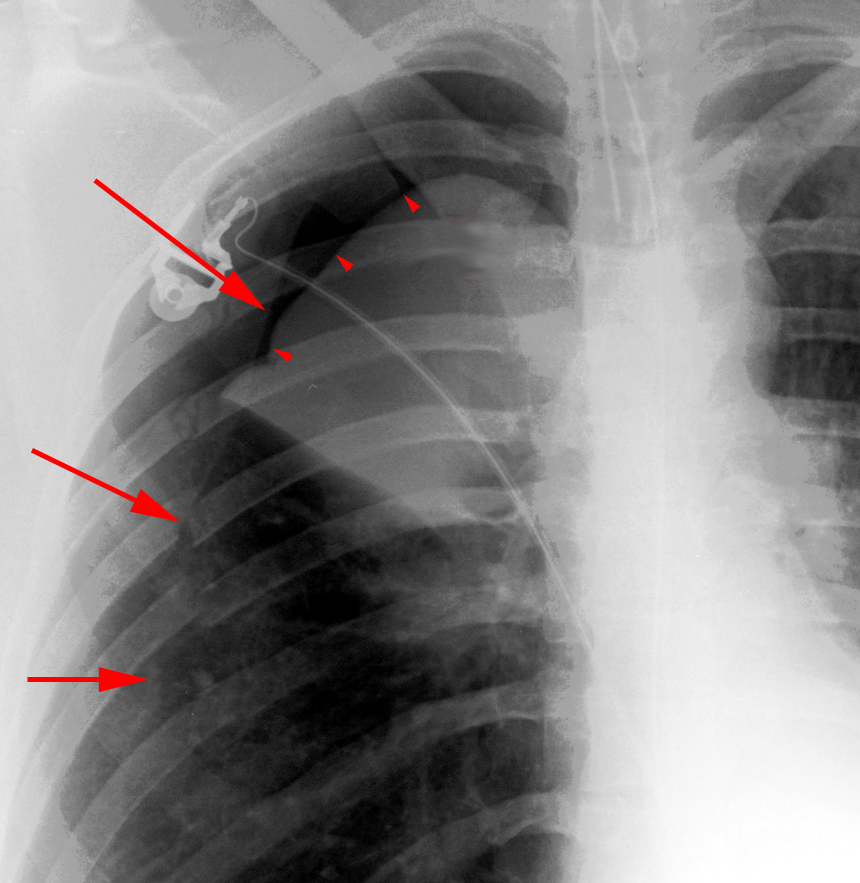

Pneumomediastinum

In the intubated patient the most likely source of air in the mediastinum is pulmonary interstitial air dissecting centripetally. Air in the mediastinum may also originate from tracheobronchial injury or air dissecting through fascial planes from the retroperitoneum. A sudden increase in thoracic pressures (e.g. blunt trauma) may also cause alveolar rupture and consequently pneumomediastinum.

Findings include; streaky lucencies over the mediastinum that extend into the neck, and elevation of the parietal pleura along the mediastinal borders.

Pneumomediastinum often dissects up into the neck. This helps to distinguish it from pneumopericardium that, unlike pneumomediastinum, can extend inferior to the heart.

Causes of pneumomediastinum include; asthma, surgery (post-op complication), traumatic tracheobronchial rupture, abrupt changes in intrathoracic pressure (vomiting, coughing, exercise, parturition), ruptured esophagus, barotrauma, and smoking crack cocaine.

Pneumomediastinum should be distinguished from pneumopericardium and pneumothorax. In pneumopericardium, air can be present underneath the heart, but does not enter the neck.

Continuois diaphram sign